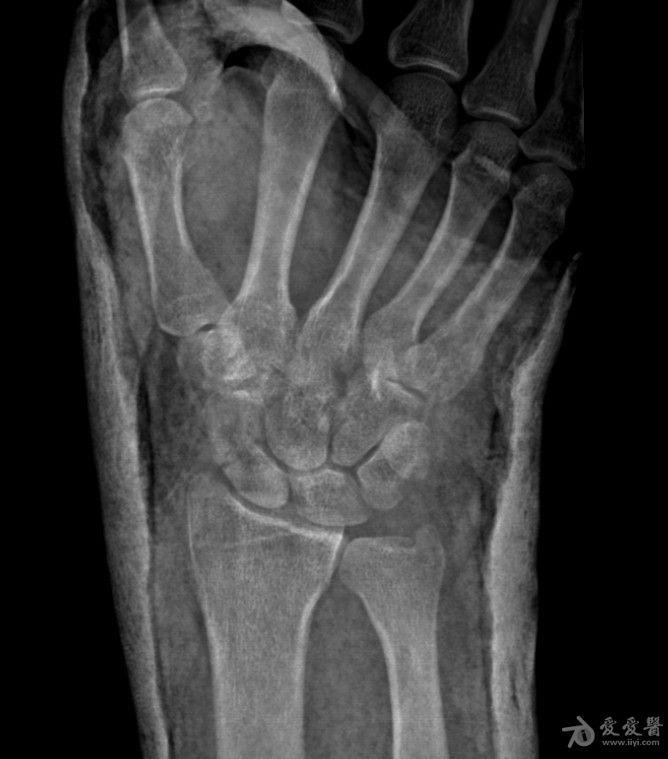

右手舟状骨骨折4个月

右手舟状骨骨折四个月,一直石膏保守治疗,拍片如下,请问,现在是手术治疗好还是继续保守治疗?